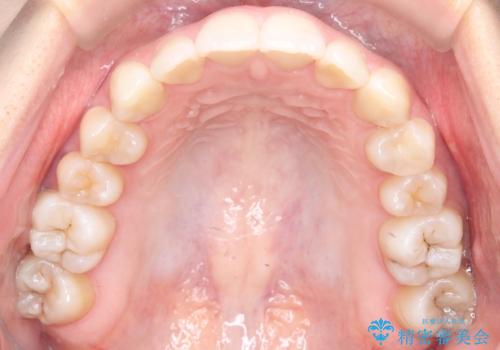

- 前歯のデコボコ(叢生)と、前歯が上下逆の咬み合わせ(反対咬合)を主訴にご来院されました。精密検査の結果、歯列全体のスペースが不足していることが判明。患者様のご希望に合わせ、透明で目立ちにくい**インビザライン(マウスピース矯正)**による治療計画を立案しました。歯を抜かずに、歯列全体を奥(遠心)へ移動させることで、歯が並ぶスペースを確保し、叢生と反対咬合を同時に改善することを目指します。

今回の矯正治療では、透明なマウスピース型の装置インビザラインを使用しました。この装置は目立たず、取り外しが可能なため、食事や歯磨きも普段通り行えます。治療は、緻密な治療計画に基づき、段階的に作製されたマウスピースを交換していくことで、遠心移動という方法で奥歯から徐々に歯列全体を後方へ動かしました。これにより、不足していたスペースを確保し、前歯のデコボコを解消。同時に、上下の歯の前後的な関係を改善することで、反対咬合も正常な咬み合わせへと導きました。見た目も機能も改善し、自然で美しい笑顔を獲得していただけました。